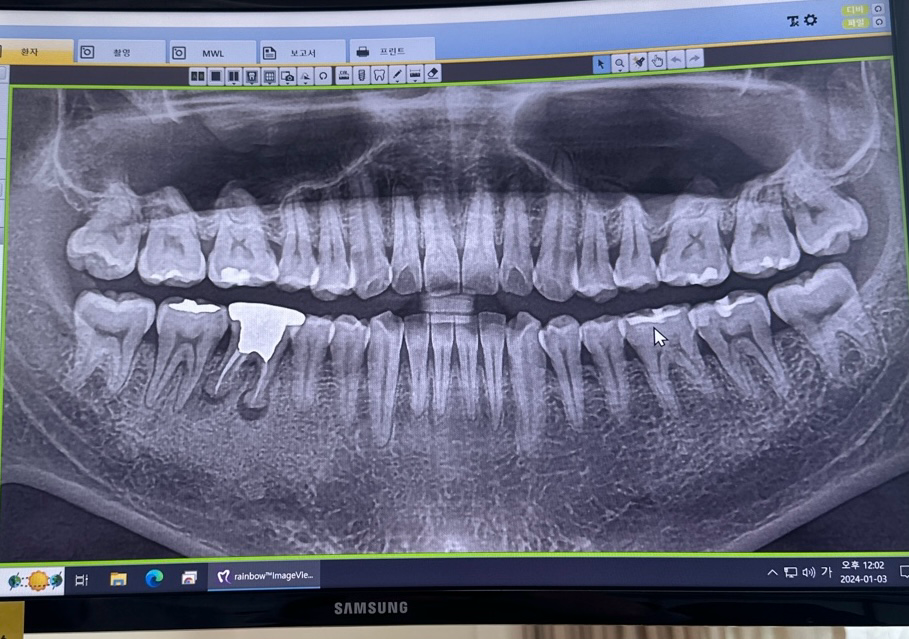

사진의 왼쪽아래부분에 뿌리가 둥그런 곤봉모양인경우에

금으로 한 20년전쯤 때운건데 거기에 구멍이 나고

아래쪽으론 염증이나서 치료는 안되고 무조건 뽑고 임플란트해야한다고합니다 맞을까요..?

20년 전에 크라운 한 치아 뿌리 끝에 병소가 생긴 것으로 엑스레이 상해서 잘 관찰이 됩니다.

환자분 엑스레이를 보았을 때, 재신경치료가 불가능 한 것은 아니나 난이도가 높은 것은 사실입니다. 치과보존과 전문의가 있는 치과를 찾아가거나 신경치료에 조예가 깊은 선생님을 찾아 보시는 것이 좋겠습니다. 그리고 재신경치료 가능여부를 상의 해보시는 것이 좋겠습니다.

사진으로 봤을 경우에는 해당치아의 뿌리 끝에 염증이 있는것으로 보입니다.

또한 과도한 힘으로 인해서 치주인대 부위가 늘어나 있는듯한 모습을 보이고 있습니다.